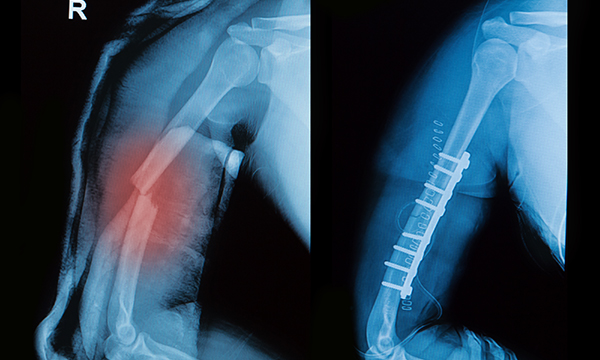

X-Ray 검사

골절선이 지속적으로 보이고, 뼈가 붙지 않은 소견 확인

내고정술 (Internal fixation)